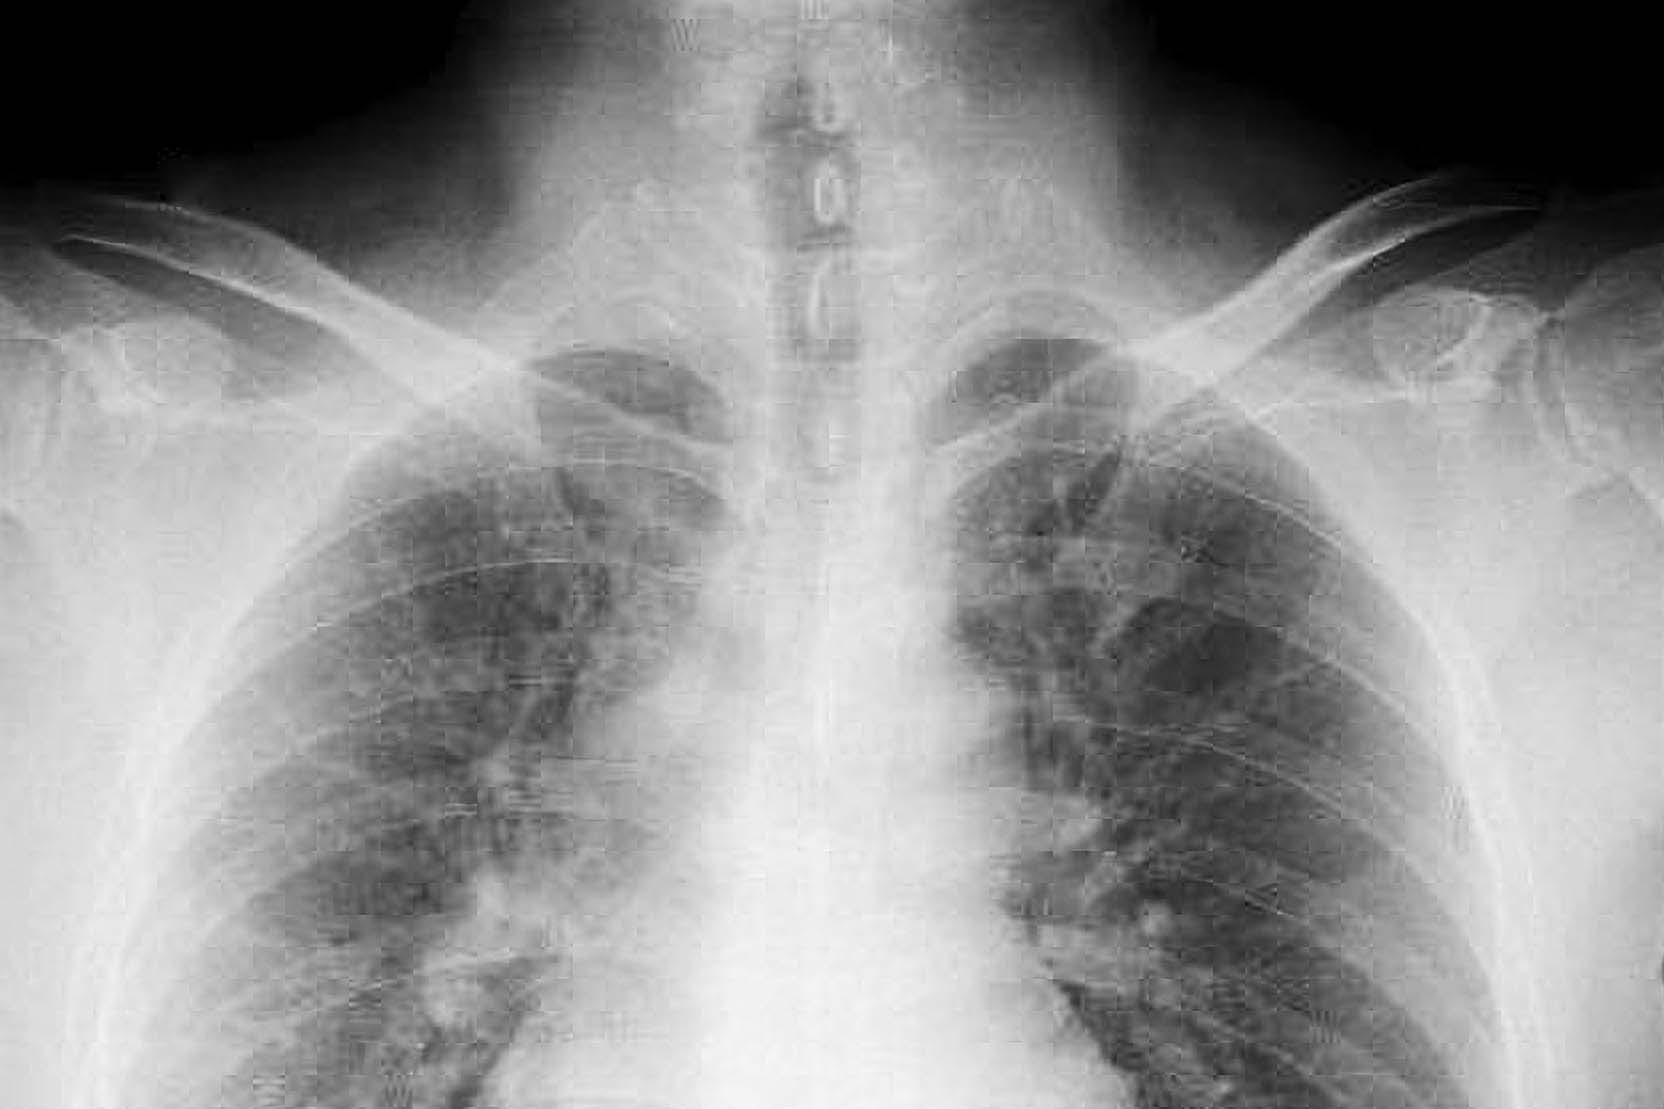

據《每日鏡報》報導,現年57歲的詹姆斯(Heather Von St James)表示,小時候在寒冷夜晚會穿上父親從工地帶回的外套外出餵寵物兔,當時並不清楚外套上的灰白粉塵其實含有石棉。直到36歲懷孕期間,她出現長期疲倦與發燒等症狀,就醫後透過電腦斷層檢查發現肺部有腫瘤,最終確診為胸膜間皮瘤(pleural mesothelioma),是一種由接觸石棉引起的侵襲性肺癌。

醫師當時告知她,若不接受手術壽命僅剩約15個月。隨後她經歷手術,切除左肺及腫瘤所在的胸膜、一根肋骨肋骨、部分橫膈膜及心臟內膜,並接受了4輪化療與30次放療,最終成功控制病情,但因僅剩單側肺部,日常生活仍受到一定影響,例如容易喘、體力下降等。